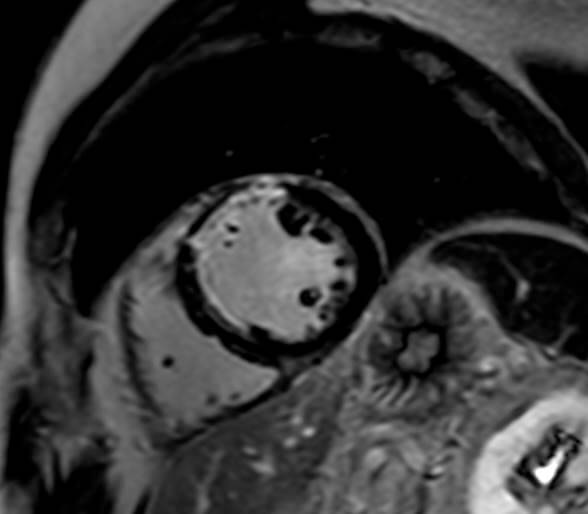

Cardiοvascular magnetic resonance exam is most often used to assess heart valve disease, congenital heart defects, cardiomyopathies, cardiac tumors, coronary artery disease and pericardial diseases.